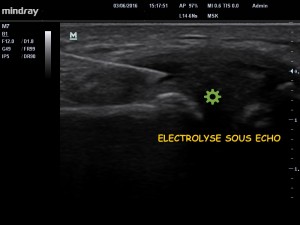

image 2. Electrolyse du ménisque.

Le traitement a consisté dans un premier temps à « électrolyser » le contenu de ce kyste sous contrôle échographique (image 2). L’électrolyse permet la formation de NaOH (soude biologique) qui a pour effet de détruite et de liquéfier le kyste , et à la formation de Cl2 et de H2 qui sont des gaz apparaissant « blanc » en échographie (image 3) confirmant la bonne exécution de la procédure .